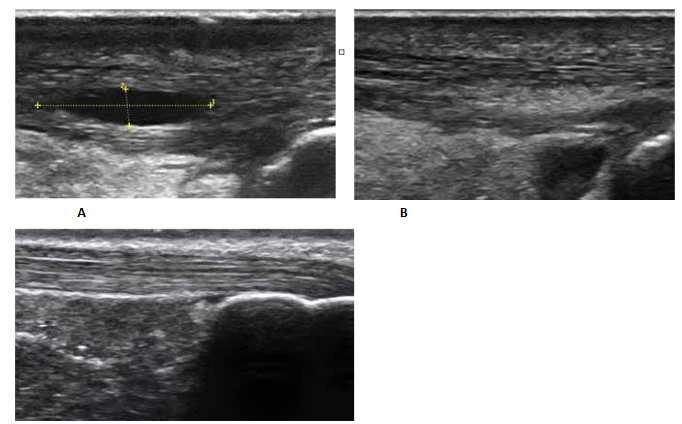

Tendon and Ligament Repair: Inclusion of several growth factors found in HD PRP, contribute to the healing of tendons and ligaments. Of importance, Nanofat stem/stromal cells can differentiate into tenocytes and limit overreaction of fibroblasts trying to form scar tissues. This aids in tendon restoration of elasticity and ligament strength are critically important in regeneration and prevention of recurrence. Further, many such regenerations result in little, or no, scarring evidence in the long-term follow up examinations and imaging.

Figure 6: Case 3: One-year post-treatment with Biocellular targeted Treatment. NOTE: Completely normal appearance of Achilles Tendon with restoration of normal echotexture of tendon without Scar formation and no bursal effusion residual.